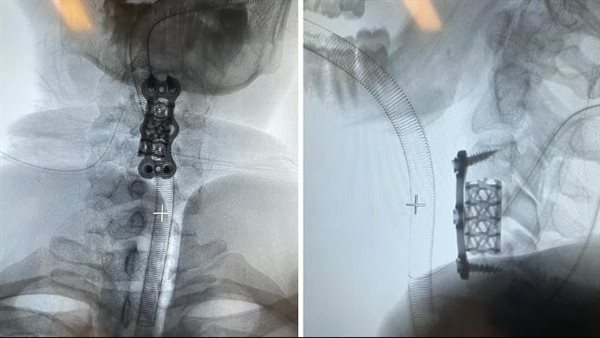

باشر الفريق الطبي إجراء ثلاث عمليات متزامنة، بدأت بإزالة الفقرة العنقية الرابعة لتحرير الحبل الشوكي، مع تركيب قفص كربوني بديل للفقرة وتثبيته بشرائح ومسامير. تلا ذلك رفع الكسر المنخسف بعظم الجمجمة وتفريغ النزيف فوق الأم الجافية، وانتهت الجراحة بتثبيت كسر الفخذ باستخدام الشرائح والمسامير.

استغرقت العمليات حوالي ثماني ساعات متواصلة، نُقل بعدها المريض إلى العناية المركزة لمدة 24 ساعة تحت المراقبة الدقيقة.